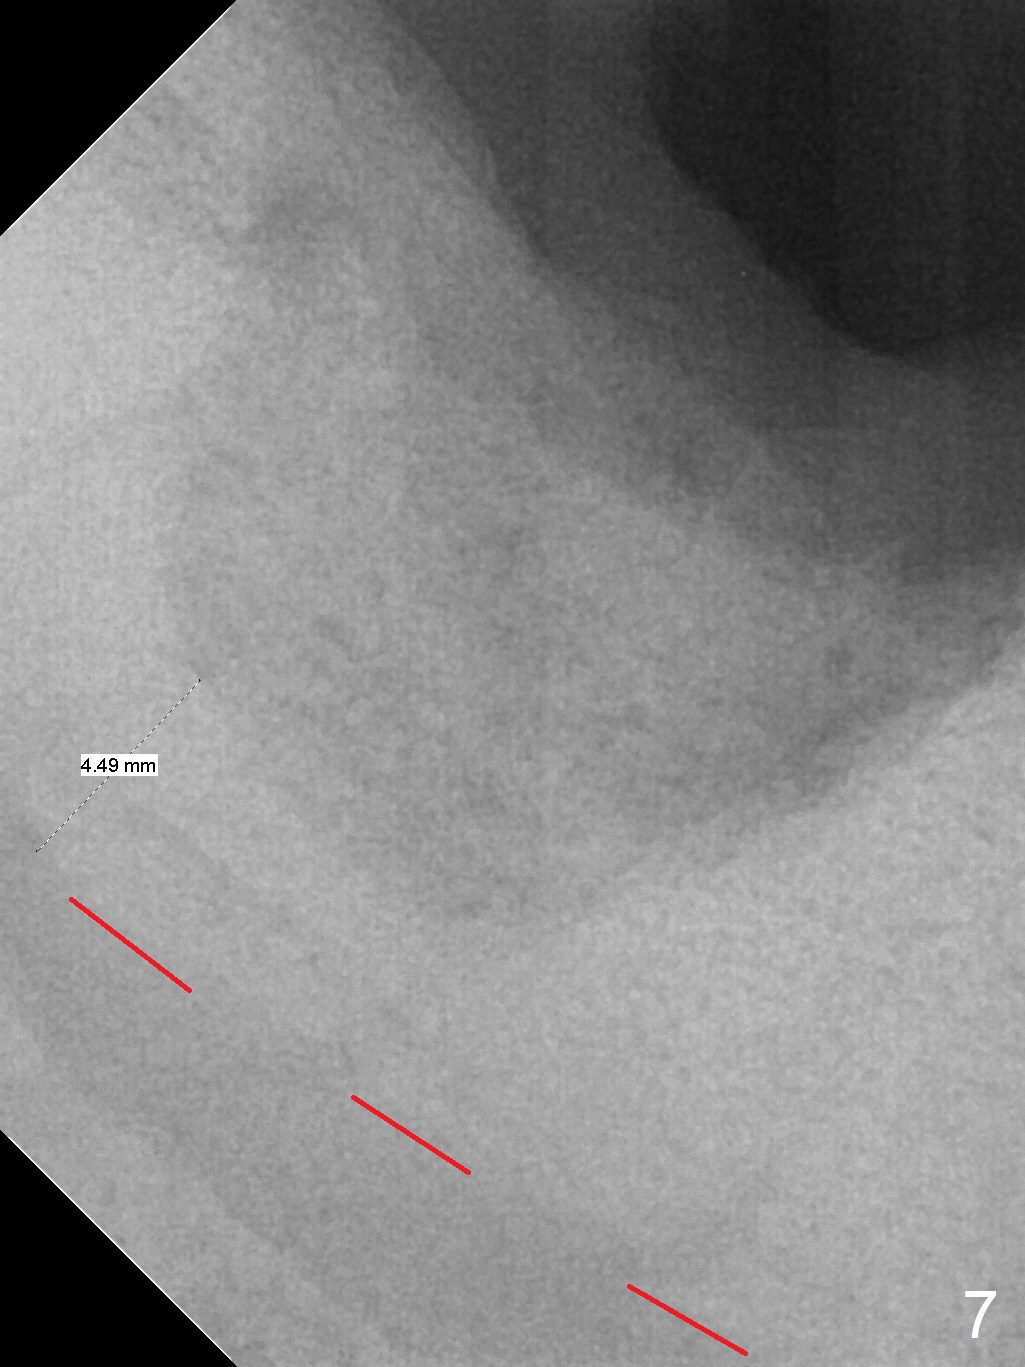

Extraction of the mobile tooth #31 (Fig.1) and debridement of the large socket are not difficult. But making osteotomy buccally does not seem to be easy. It will be difficult to restore. Instead, socket preservation is accomplished by filling the socket with approximately 1.5 cc of Mineralized Cortical/Cancellous allograft until the crest (Fig.2,5). The socket opening is closed by insertion of 4 pieces of PRF membranes (Fig.3) and 4-0 Chromic gut sutures (Fig.4). In the end of surgery, it appears that osteotomy in the center of the socket could be a better approach. Postop re-analysis of CT (Fig.6) and PA (Fig.7) shows that there is 3.9 mm of the native bone to support a 5.5x10 mm implant. Sinus Lift Master Kit should be used with 2 mm initial drill and 2.8 and 3.6 mm round drills with 4 mm stopper.

The socket heals 3 months postop (Fig.8,11). There is vertical loss of the ridge at #31 (Fig.9,10). The implant placed at #31 will be shorter than that at #30 (Fig.12). The patient will return for implant placement 4 months postop.